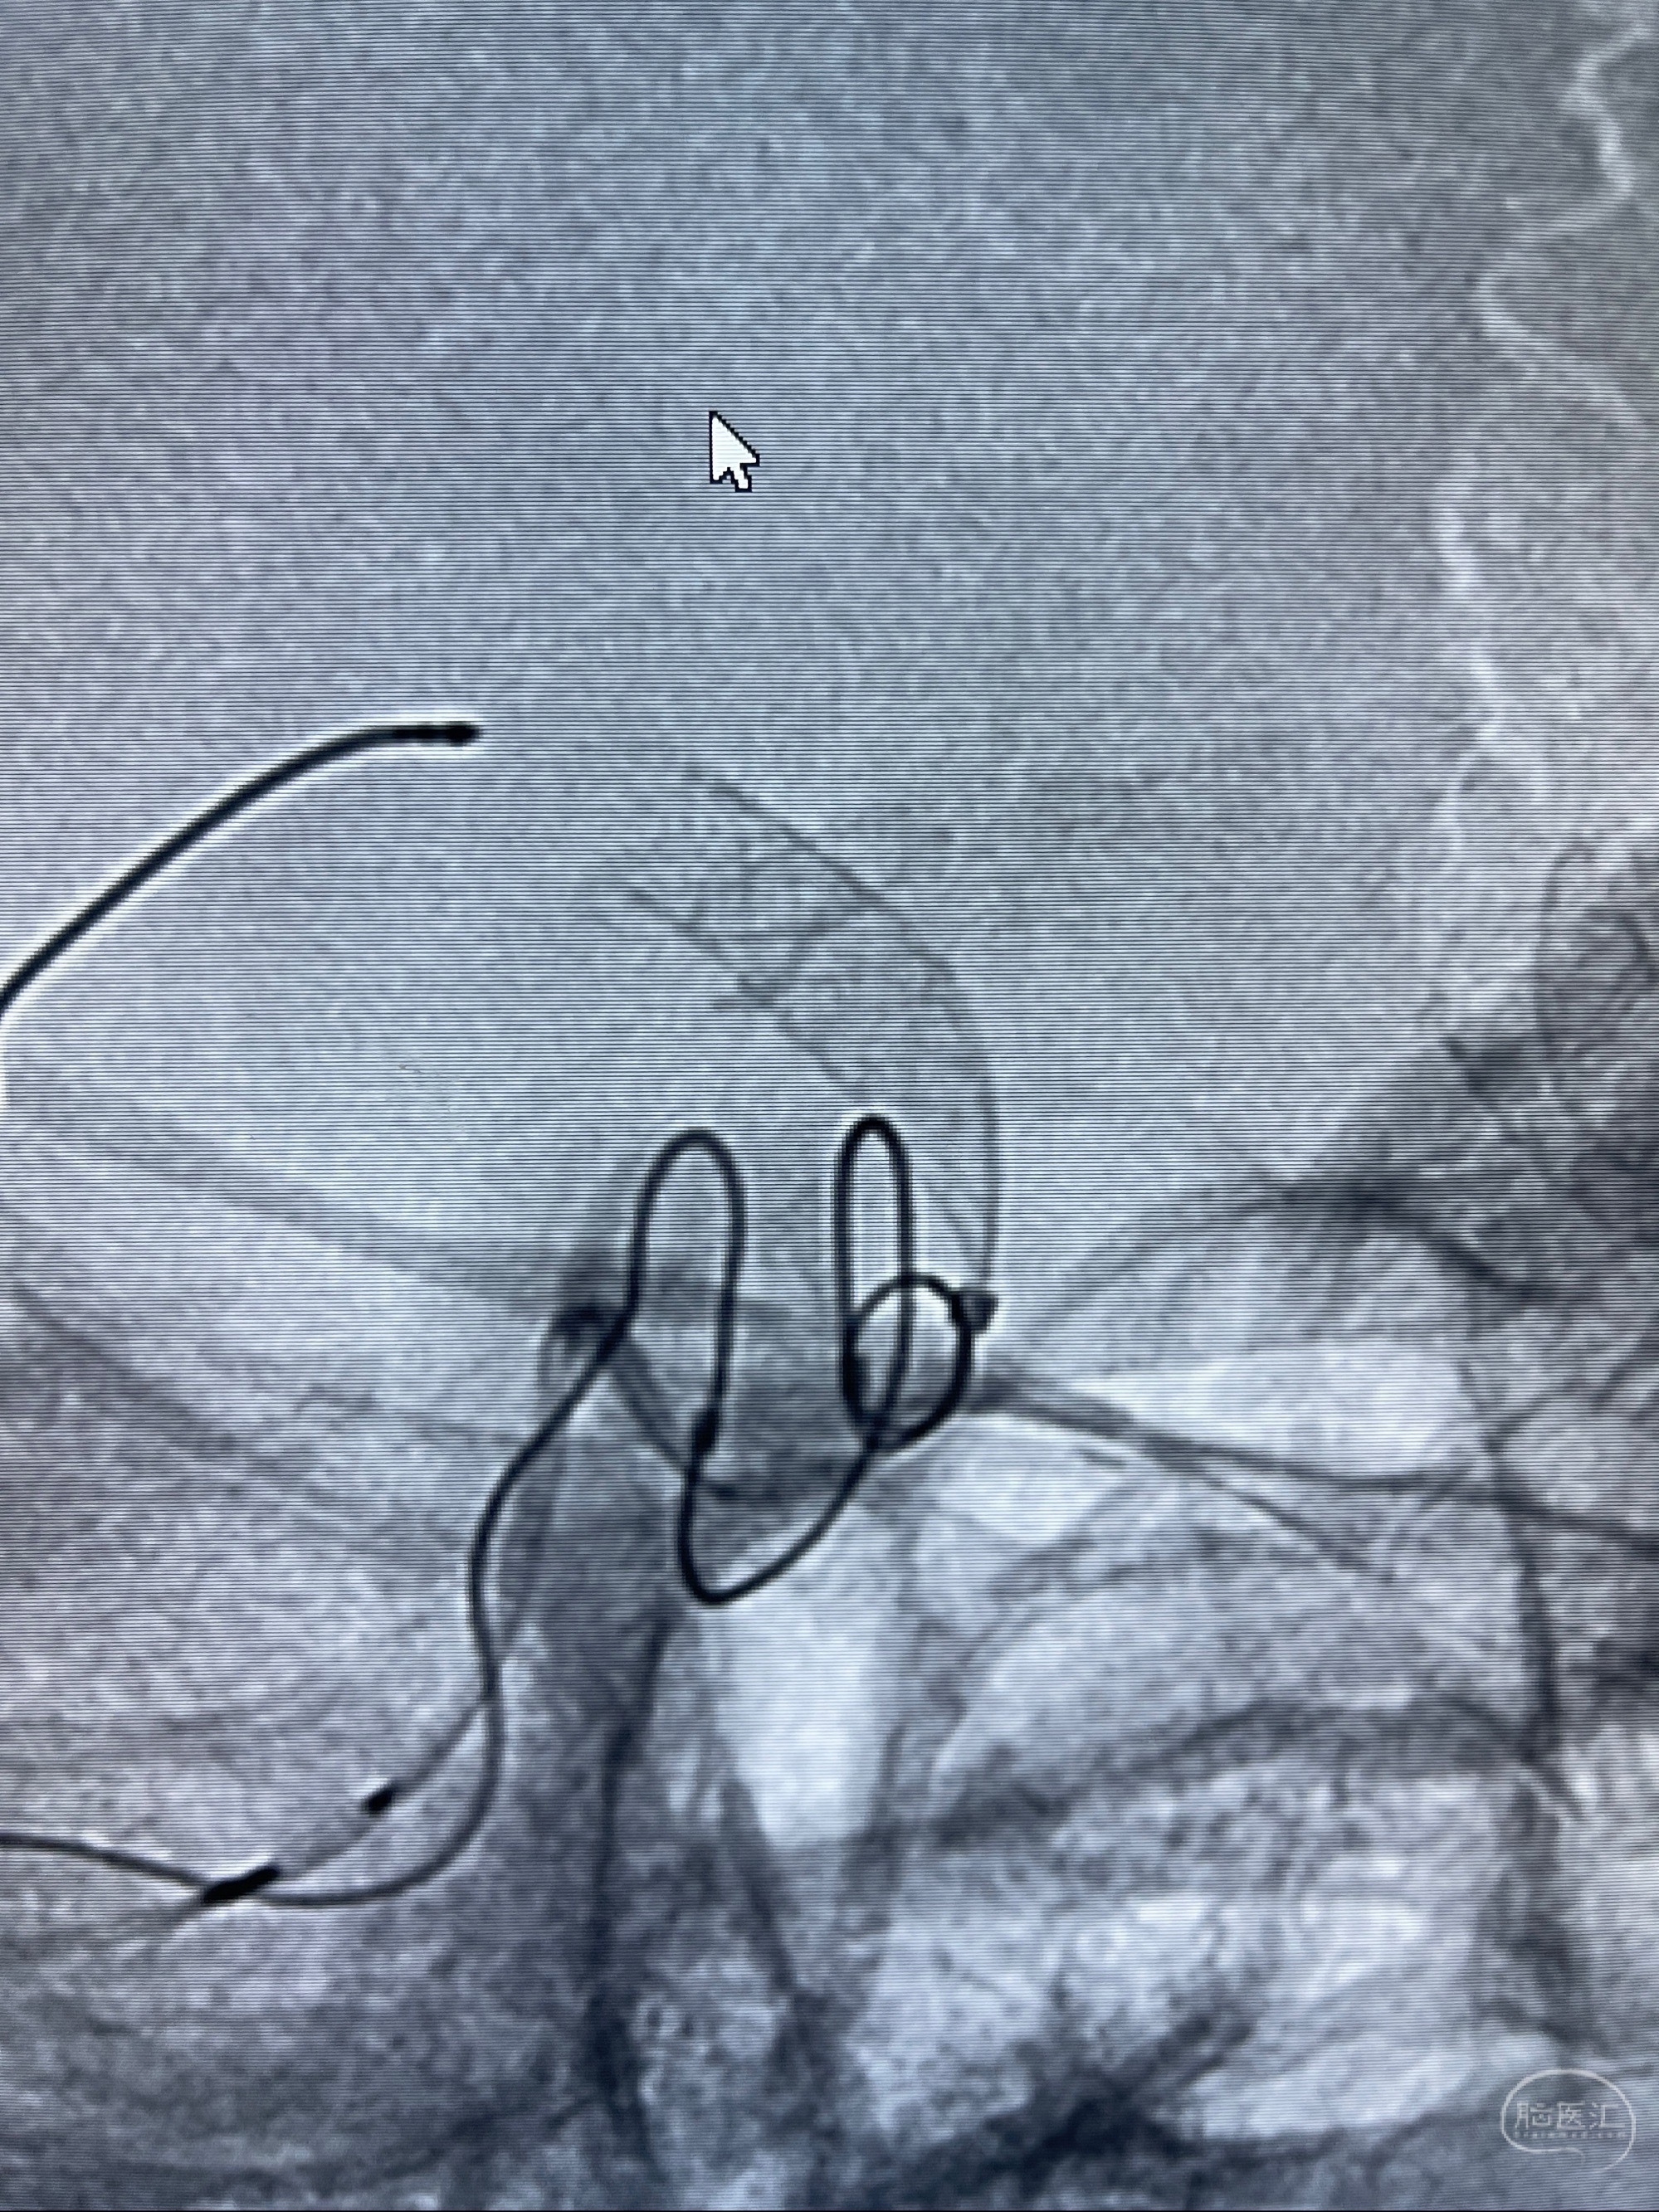

2023-07-27全脑血管造影:双侧颈内动脉眼动脉段动脉瘤,右侧较大

2023-08-01全麻下行双侧颈眼动脉瘤支架辅助栓塞

- pipeling4.5-20mm

- pipeline 4.0-20mm